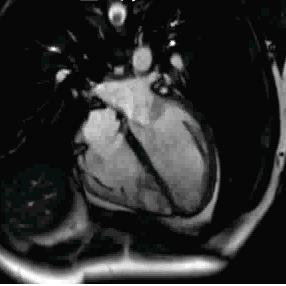

这是我们心脏正在跳动